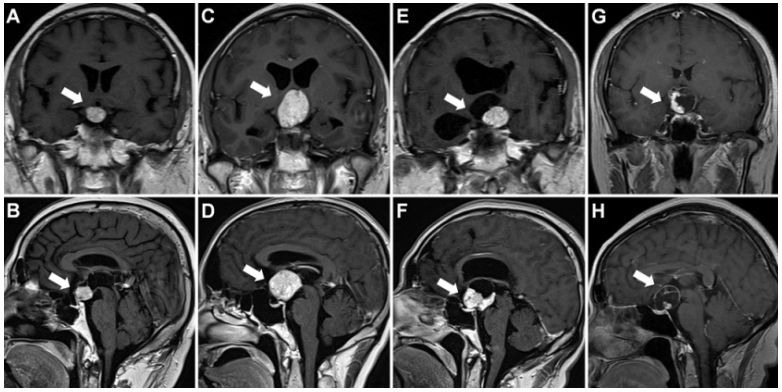

4.通过MRI成像识别BRAF突变型颅咽管瘤

Prediction of BRAF mutation status of craniopharyngioma using magnetic resonance imaging features.

PMID: 28984520 DOI: 10.3171/2017.4.JNS163113

通过52例颅咽管瘤患者的MRI特征,预测BRAF突变。经对比发现,BRAF突变型颅咽管瘤比BRAF野生型颅咽管瘤有更易鞍上生长、呈球型、主要为实质性结构、均匀强化和垂体柄增粗等显著的5个MRI表现特征。